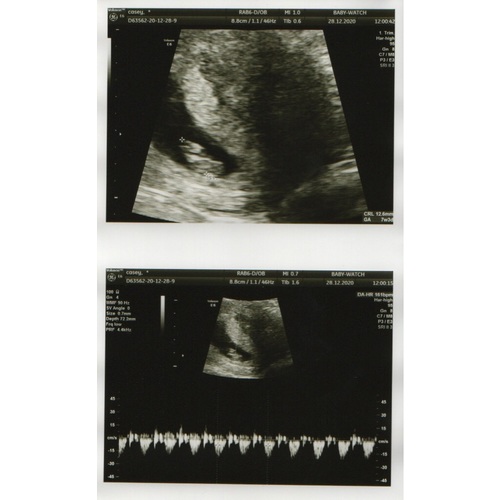

Hier onze echo met 7 weken. Links is de dooierzak, rechts de baby. Wij zagen echt een soort flikkerend lampje, dat was het hartje 馃グ Bij mij was het ook een inwendige echo, maar dat voel je amper. Stuk minder koud dan het echoapparaat op je buik in ieder geval 馃槄 hahaha

Dit is een echo van 7w wel niet de mijne is van een app. De echo is inwendig en je zal normaal een kloppend hartje zien.